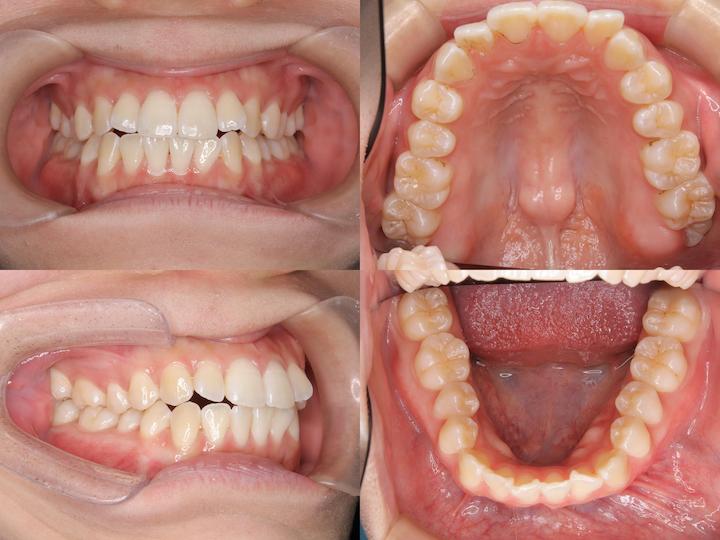

反対咬合のハーフリンガル矯正

Before

After

治療期間: 1年8カ月

前歯の反対咬合と下顎骨の右側偏位を、左下4番抜歯を伴うハーフリンガルで治療しました。

初診時年齢3110ヶ月の患者様です。前歯の反対咬合と下顎骨の右側偏位に対し、左下4番目の歯を抜いてスペースをつくった後、下の前歯を左後方に移動しました。上の歯は裏側に、下の歯には表側に矯正装置をつけるハーフリンガル矯正を行いました。治療後は反対咬合も改善され、噛み合わせたときに上の前歯が下の前歯よりも前にくるようになりました。また、上下の歯の中心も合わせることができました。

反対咬合を改善させる過程では、前歯の干渉により、咬合性外傷(噛み合わせの力が強いことによって歯や歯周組織、顎関節などを損傷すること)を生じるリスクがあります。そのため、こちらの症例では奥歯の高さを調整することで前歯の当たりを調整しながら治療を進めました。